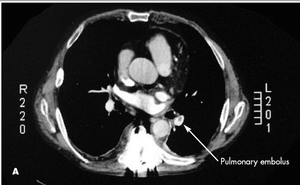

A 59-year-old man presented with painful paraparesis of acute onset, severe low back pain, and shortness of breath. On initial examination, he had 0/5 strength and numbness in his lower extremities. The skin from below his umbilicus to his lower legs was pale.